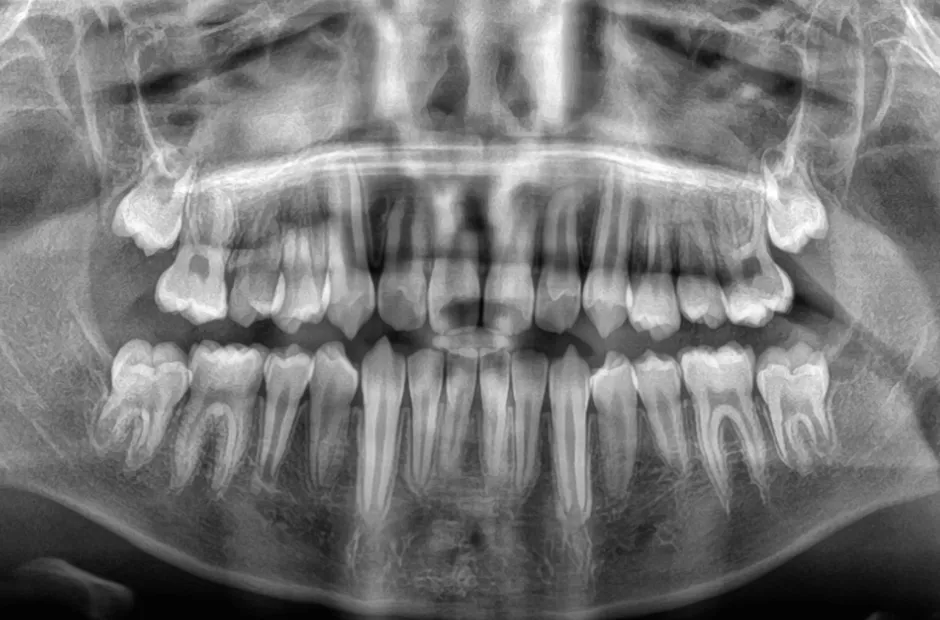

口腔内写真やレントゲンの撮影、歯型取りなど、口や顎の状態を詳しく把握するための精密検査を行ないます。さらに、骨の成長状況や身長・体重の増加傾向、永久歯の生えかわりについても確認します。

永久歯の数が足りない

(先天性欠如)

先天的に永久歯が不足している状態を先天性欠如といいます。先天性欠如があると、すきっ歯になったり、乳歯が抜けずにそのまま残ったりすることがあります。すきっ歯の場合は、矯正治療ですき間を閉じることで、将来的にブリッジやインプラント、入れ歯が必要になる事態を回避できる可能性があります。歯科検診で指摘されるまで気づかれないことが多く、放置すると高確率で歯並びや噛み合わせに悪影響を及ぼします。調査によると、先天性欠如歯は10人に1人の割合で見られ、近年増加傾向にあります。

6本以上永久歯が無い方は、矯正歯科治療が保険適用になります。